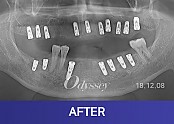

임플란트 181210